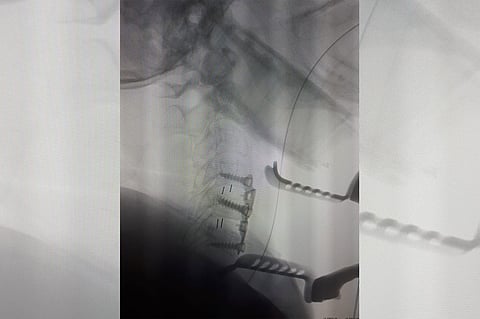

وقرر الطبيب المعالج إجراء تدخل اجراحي، بعملية تضمنت دمج وتثبيت الفقرات بواسطة دعامات وشرائح وتكللت بالنجاح؛ حيث عادت المريضة للتحكم بالأطراف المتضررة، وغادرت بعد ذلك المستشفى وهي بصحة جيدة.